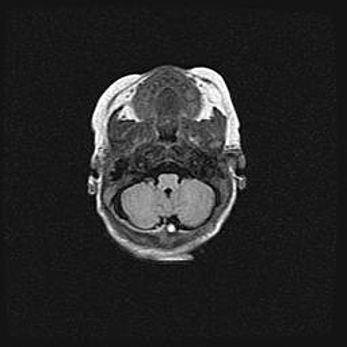

Подострая гематома правой гемисферы мозжечка.

Наружная гидроцефалия.

Возраст: 15 дней

Вес: 3100 г

Пол: женский

Окружность головы: 37 см

Срок гестации: 35-36 недель

При открытой наружной форме гидроцефалии у новорожденных расширяются и переполняются субарахноидные пространства.

Кровоизлияния в мозжечок имеют две клинико-анатомические формы: полушарные гематомы и кровоизлияния в червь.

К появлению этой патологии может привести: повреждения головного мозга, возникающие в результате асфиксии и гипоксии плода при беременности, или травмы во время родов. Редко гематома мозжечка может быть результатом первичной коагулопатии и сосудистой мальформации, диссеминированном внутрисосудистом свертывании, изоиммунной тромбоцитопении.